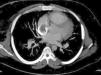

Inicialmente, se considera que cursaba con angioedema por lo que se inicia manejo con antihistamínico y corticoide, oxígeno suplementario, con lo cual se obtiene mejoría parcial, por lo que se establece como diagnóstico diferencial del síndrome de la vena cava superior. Entre los hallazgos positivos se encontró hipercapnia (PcO21 37,4mm Hg), gradiente alvéolo arterial aumentado (50,7), poliglobulia (Hb2 20,6, HCto3 65%) y LDH4 elevada (460). En la tomografía del cuello se descartan masas, se complementa el estudio con la angiotomografía del tórax, la cual evidencia un gran trombo oclusivo que compromete la vena cava superior, con extensión a su desembocadura en la aurícula derecha, tromboembolia pulmonar con compromiso segmentario en el lóbulo inferior izquierdo asociado a consolidaciones parenquimatosas, probablemente, por infartos pulmonares, probable hipertensión pulmonar precapilar y dilatación tanto auricular como ventricular derecha (figs. 1 y 2).